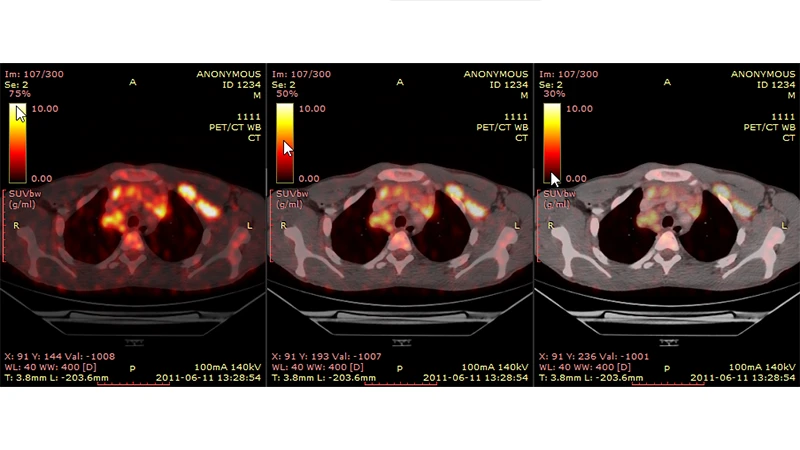

Modern scanners often combine PET and CT into a single hybrid machine (PET/CT). The patient undergoes both a PET scan and a CT scan in one session. The resulting images are then fused together by a computer. This provides the best of both worlds: the PET scan shows areas of high metabolic activity (the function), and the CT scan provides the detailed anatomical map (the form), allowing a radiologist to see exactly where the physiological activity is occurring.

- Oncology: Detecting cancer, determining if it has spread (metastasized), and monitoring the effectiveness of treatment. FDG-PET/CT, which uses a radioactive glucose analog, is a cornerstone of modern cancer imaging.